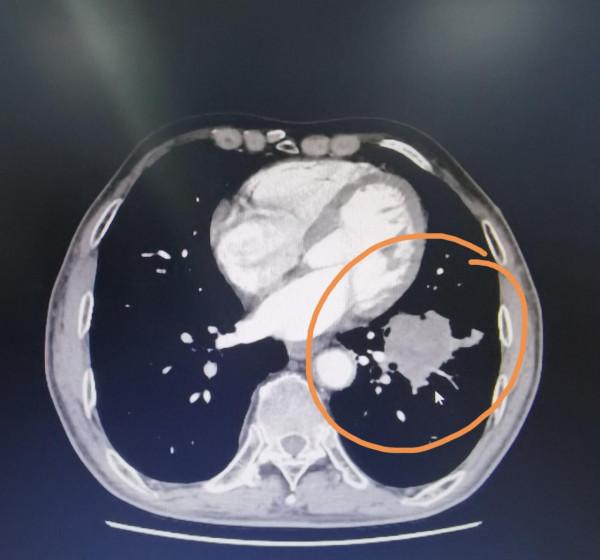

這是一個家住天津市東麗區67歲的男士,半個月前因為在家裡幹農活,自覺用力大了一些,左側的手臂開始疼,呆了幾天,疼痛越來越厲害了。到醫院來檢查,發現左側的尺骨有一個腫瘤。骨科醫生給做了一個全面的檢查,發現了左下肺有一個將近6釐米的佔位,雙肺還有一些多發的結節。雙側腎上腺也能看到腫瘤。從胸部的片子來看,首先考慮像是肺癌,腎上腺以及雙肺的其他結節還有尺骨的這個腫瘤是不是肺癌轉移過來,我覺得很有可能。

我問這位患者平時抽菸麼?他說我從16歲就開始抽菸。我又問他,每年去體檢嗎?查過體嗎?他說從來沒有查過體,沒照過胸部的片子。我仔細問了一下他胸部的症狀,咳嗽,胸痛,憋氣等等他現在都沒有。大家透過這個病例可以知道,不是肺上有了東西,就一定有胸部的症狀。臨床上我手術過的患者,有的肺上長了10釐米的瘤子,但病人一點症狀沒有。因此單憑自己沒有症狀,就斷定自己沒有問題,您覺得靠譜嗎?